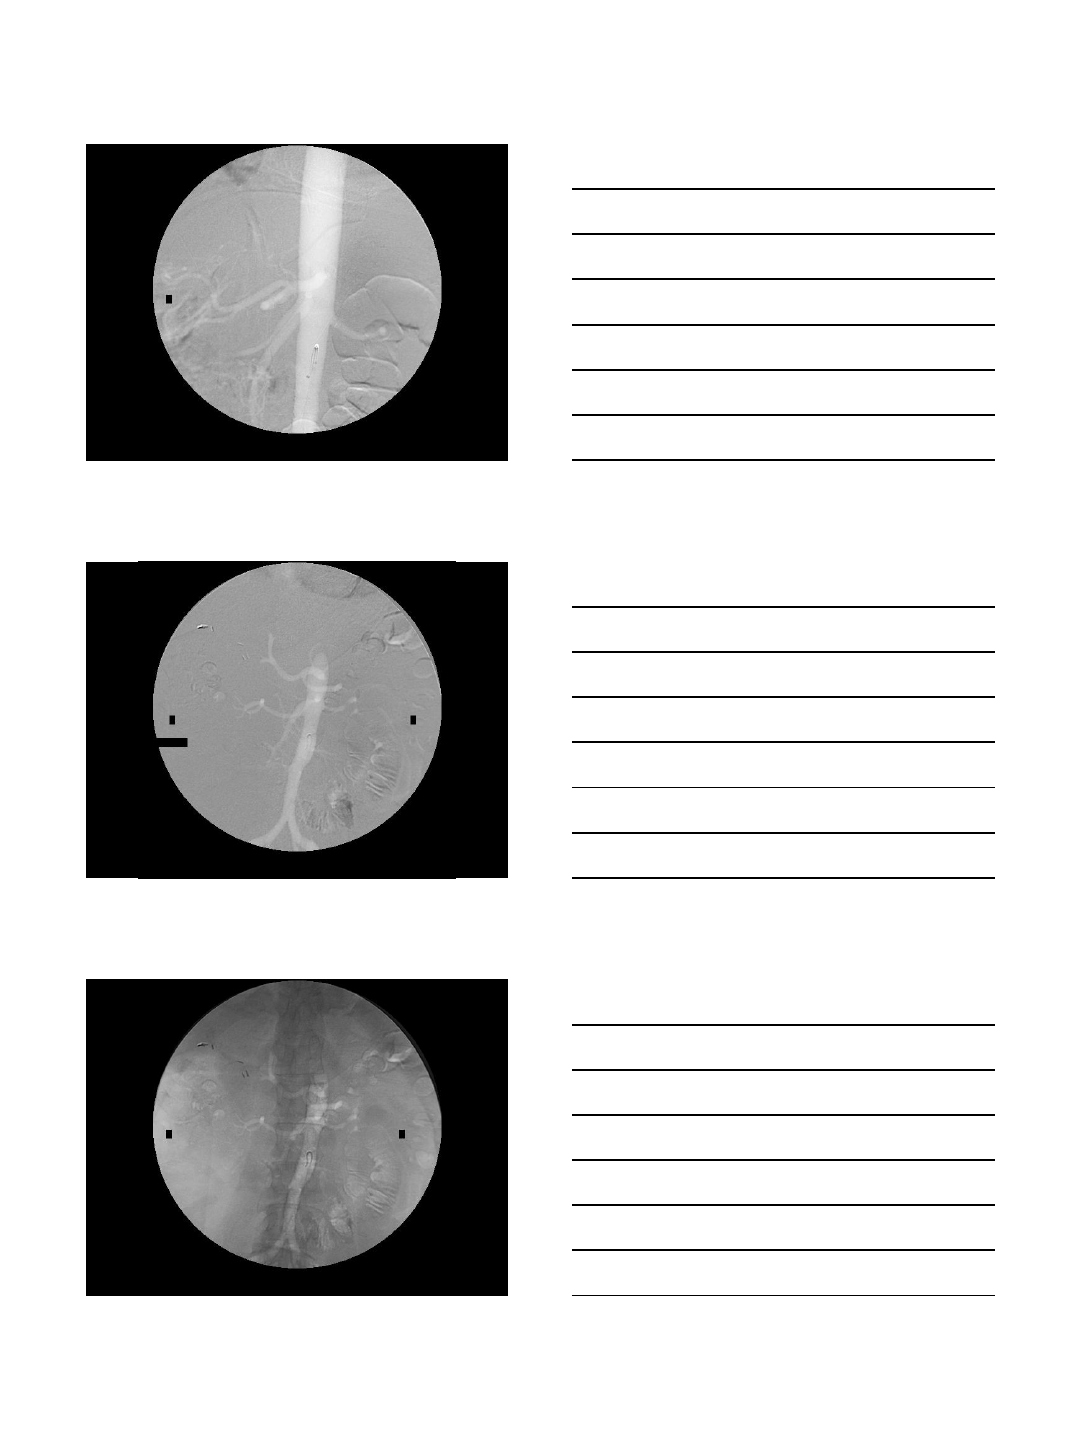

DIALYSIS ACCESS INTERVENTION

Case Presentation

•68 year old woman with ESRD

•On hemodialysis via an AV fistula

•Allergic to iodinated contrast

•Refractory to pre-medication

•Ongoing problems with her AV fistula

•Bleeding post-dialysis

•Requires 3 month-surveys

CO2 Fistulogram

•This patient’s procedures are

completed whenever necessary without

the use of contrast medium

•No further allergic reactions